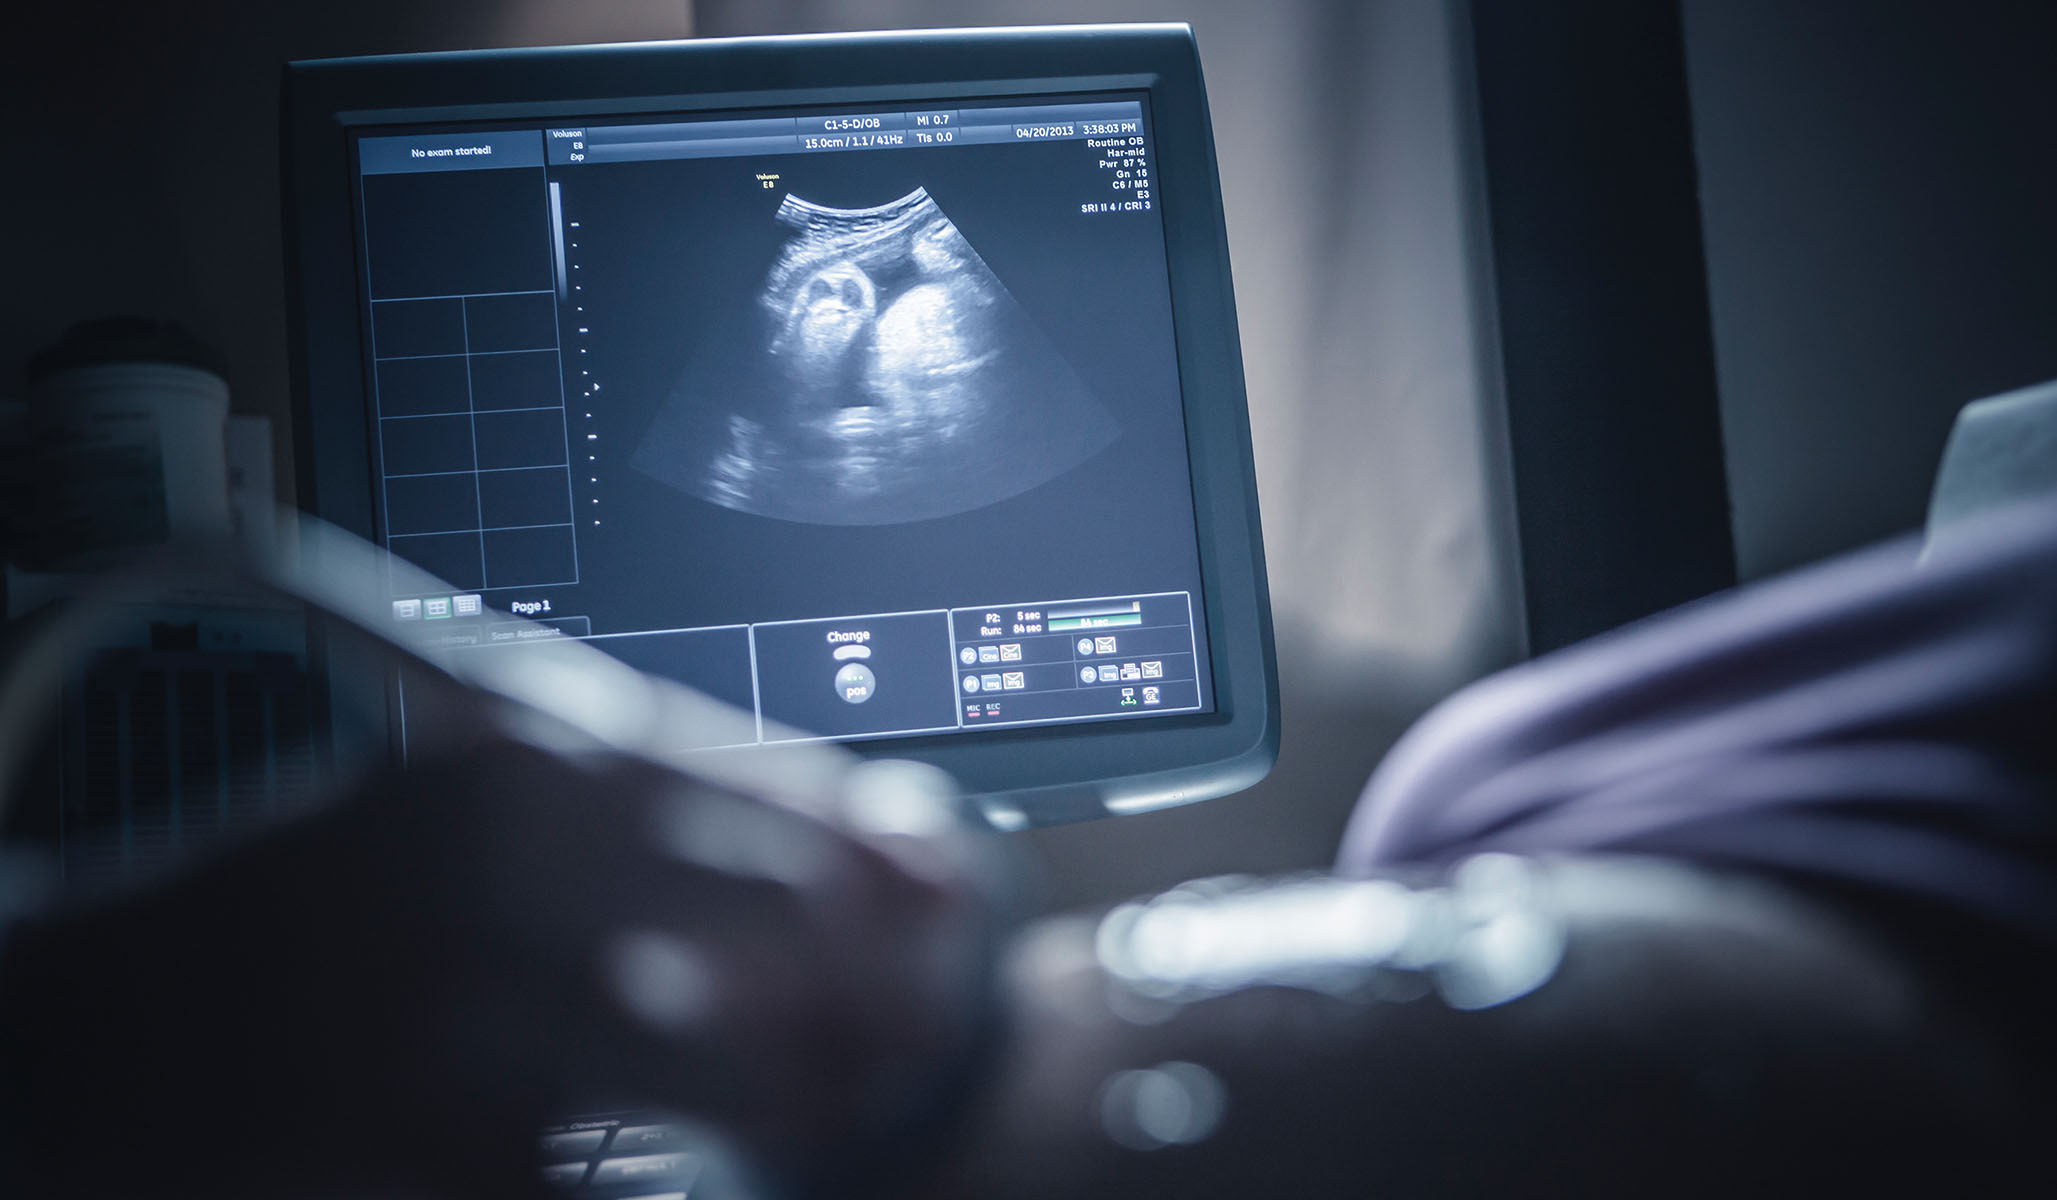

Infants born as early as 21 weeks to 22 weeks of pregnancy have survived their stays in the neonatal intensive care unit and grow up to be healthy children. But Hern makes a living by killing preemies “who are 22, 25, even 30 weeks along,” according to the Atlantic’s Elaine Godfrey. Most of the time, these babies and their mothers are physically healthy: “Abortions that come after devastating medical diagnoses can be easier for some people to understand. But Hern estimates that at least half, and sometimes more, of the women who come to the clinic do not have these diagnoses.”